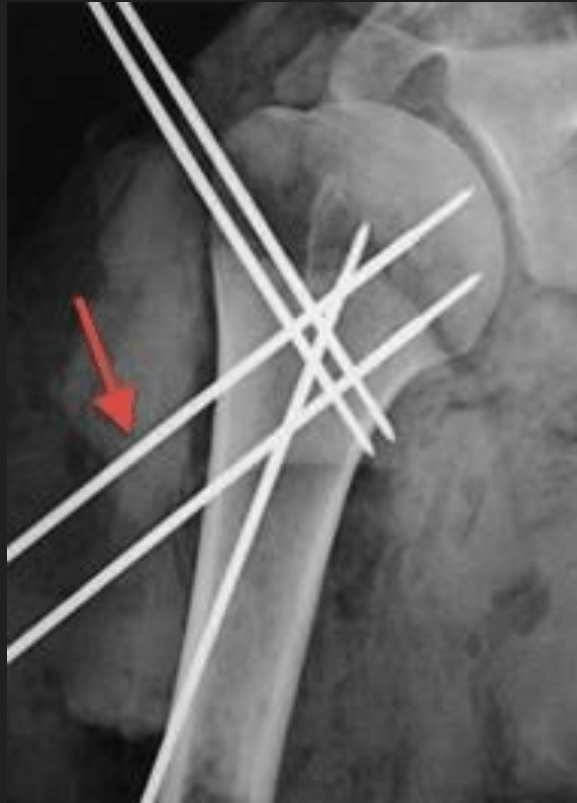

A 60-year-old woman is undergoing closed reduction and percutaneous pinning of a proximal humerus fracture. What structure is at greatest risk for injury from the pin marked by the red arrow in Figure A?

Axillary N.